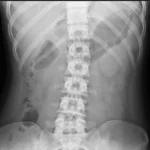

X-ray remains the most widely used diagnostic imaging modality worldwide. In Dubai, it serves as the essential first-line investigation for a broad range of clinical concerns, from sports injuries and workplace accidents to chronic conditions like osteoarthritis and scoliosis. Our digital radiography system captures high-resolution images that allow radiologists to detect subtle findings that older film-based equipment might miss.

Back pain or spinal alignment concerns

Scoliosis & Spinal Alignment

Full-spine X-ray is the standard imaging tool for measuring spinal curvature, monitoring progression in adolescents, and planning treatment strategies.